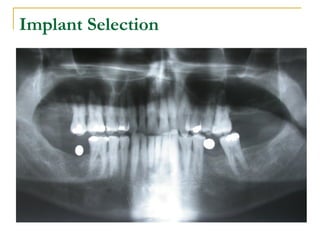

Implant Selection

Influence of implant diameter and length

on crestal stress distribution

 1). Greater the diameter of the dental

implant less the crestal bone stress.

 2). Greater the length of the implant less

the crestal bone stress.